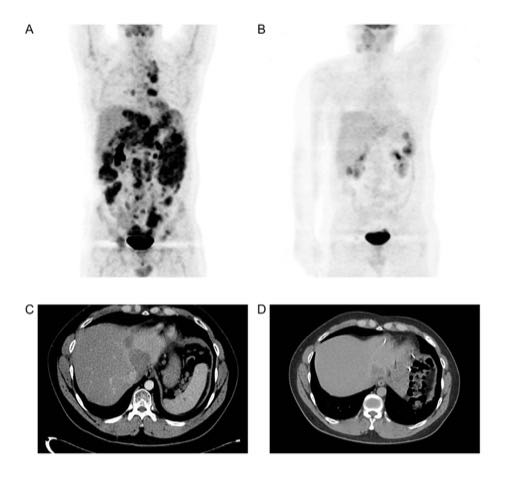

在针对NK010的临床试验中,多名预计生存期仅2-6个月的铂耐药晚期卵巢癌患者,通过NK细胞治疗显著延长了生存时间。

其中一位患者的故事尤为鼓舞人心。该患者于2014年确诊晚期卵巢癌,历经手术、化疗,病情仍不断进展。2019年入组NK细胞治疗临床研究时,体内已有多个转移病灶。经过13次NK细胞治疗,截至2020年9月,患者已存活超过40个月,且影像学检查显示病灶明显缩小甚至消失。